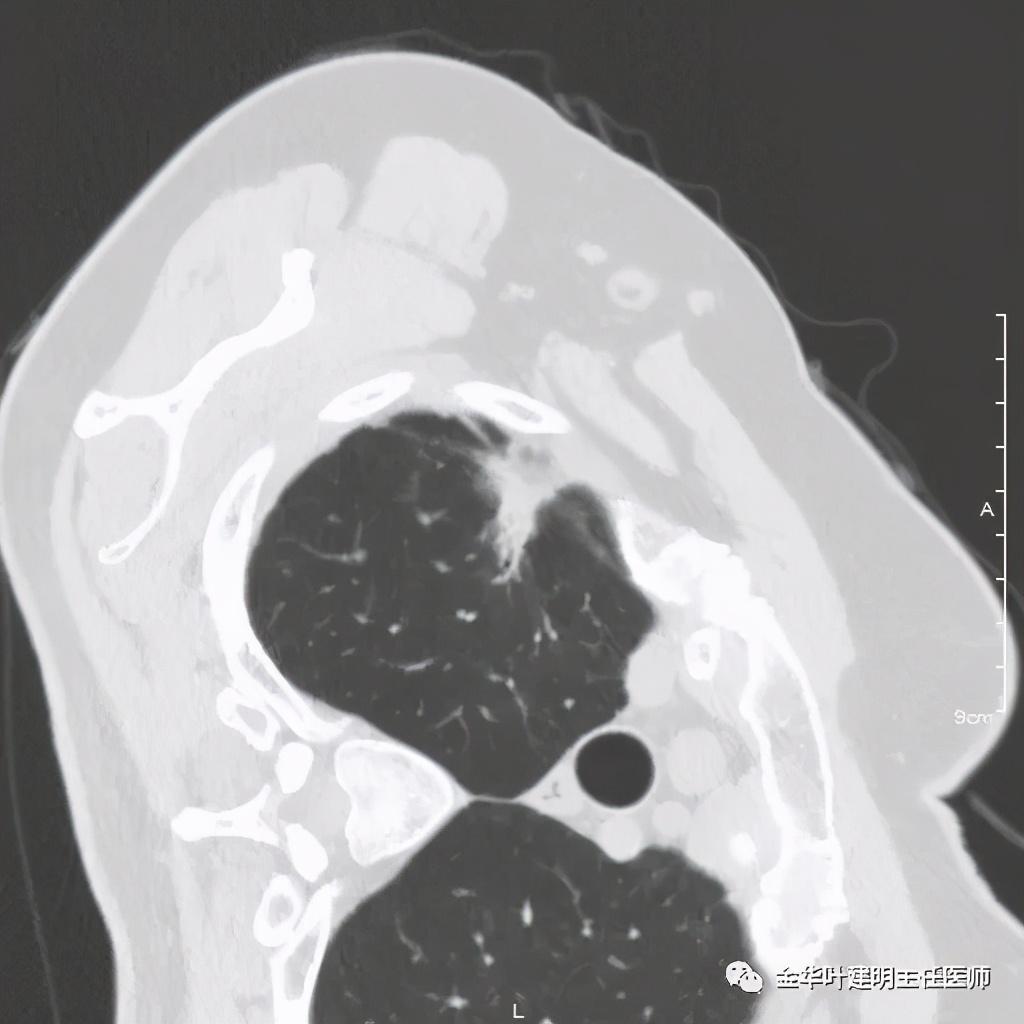

六、神经内分泌癌(此例为不典型类癌,小细胞癌以后再总结):

影像特征:不典型类癌一般圆形生长,实性,边缘比较光滑,但硬度不够。侵蚀力也不够。就像这例,我们发现其与肺动脉接触的地方,居然无法推压血管,反而肿瘤被血管占据了其生长的位置,在支气管内,肿瘤也是对支气管壁没有造成明显的破坏。也就是说 圆形边清较软、侵蚀力弱的实性结节 要考虑类癌的可能性。